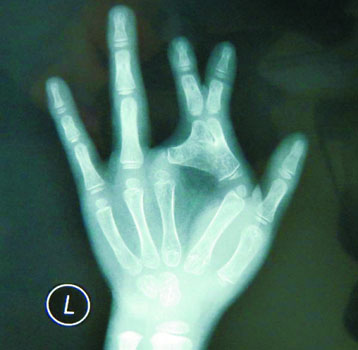

“普通的并指骨骼是分开的,但是小娜却因为骨关节严重畸形而骨骼连在一起。”小娜的主治医师儿童医院烧伤整形科田晓菲说,小娜的“剪刀手”与普通骨性并指相比,手术难度要大得多,其左手二、三指属于异常畸形的并指,形成一把剪刀状,伴手指发育不良,指骨弯曲。目前,经过田晓菲医生的精心手术,小娜左手终于恢复正常。